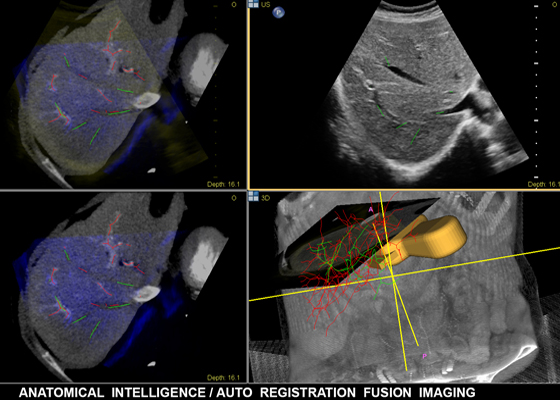

Функция интеллектуального определения анатомических структур изучает данные УЗИ пациента и применяет адаптивную интеллектуальную логику системы с использованием трехмерных анатомических моделей для создания более простых и воспроизводимых результатов. Инструменты интеллектуального определения анатомических структур, например HeartModel, используют усовершенствованное моделирование органов, формирование срезов изображений и надежный количественный анализ, помогая упростить проведение УЗИ, обеспечивая более высокую воспроизводимость, предоставляя при этом клиническую информацию нового уровня для решения экономических и клинических задач, возникающих в условиях современного медицинского учреждения.

Интеллектуальное определение анатомических структур применяется в таких решениях компании Philips для визуализации, как EPIQ, Affiniti и EchoNavigator. Оно предоставляет врачам современные и одновременно простые в применении инструменты обработки и помогает им быстро и более уверенно определять анатомические структуры и патологии, оценивать состояние заболевания, назначать лечение и контролировать проведение процедур.